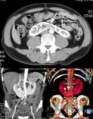

肾融合